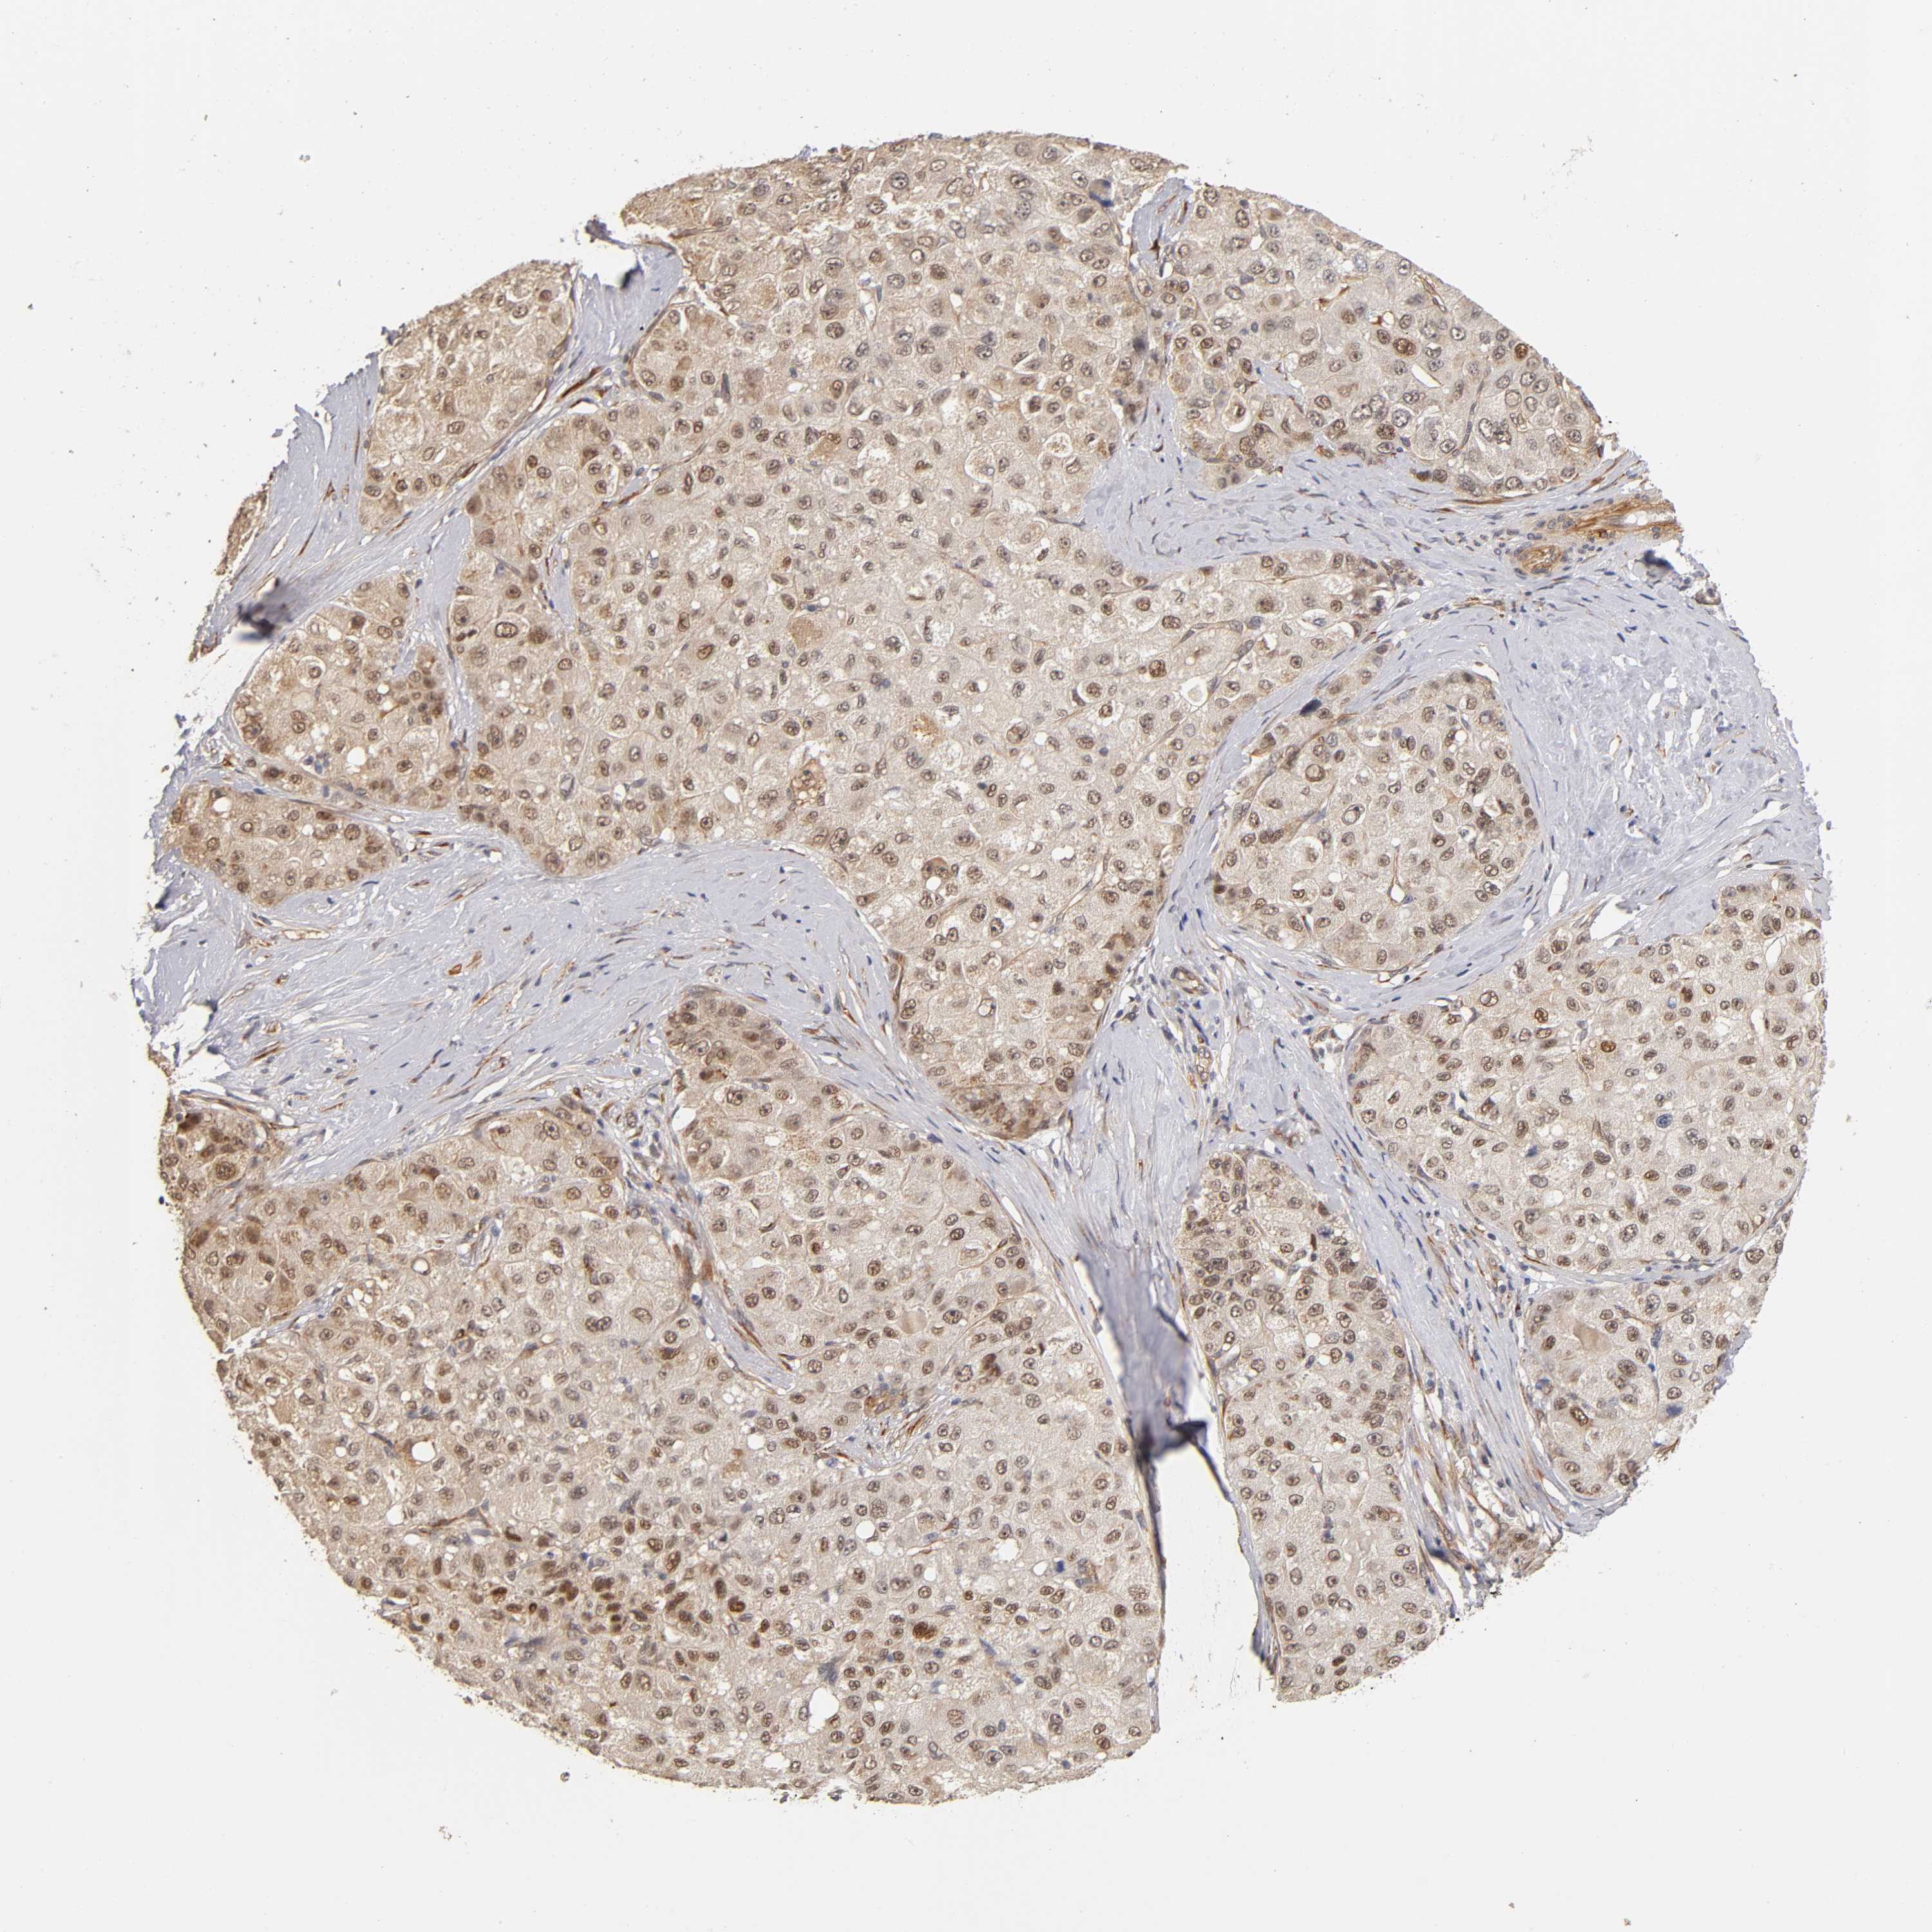

LIVER CANCER - Protein expressioni

A mouse-over function shows sample information and annotation data. Click on an image to view it in a full screen mode. Samples can be filtered based on level of antibody staining by selecting one or several of the following categories: high, medium, low and not detected. The assay and annotation is described here.

Note that samples used for immunohistochemistry by the Human Protein Atlas do not correspond to samples in the TCGA dataset.

Antibody stainingi

Antibody staining in the annotated cell types in the current human tissue is reported as not detected, low, medium, or high, based on conventional immunohistochemistry profiling in selected tissues. This score is based on the combination of the staining intensity and fraction of stained cells.

Each image is clickable and will lead to virtual microscopy that enables deeper exploration of all samples and also displays staining intensity scores, fraction scores and subcellular localization as well as patient and tissue information for each sample.

Antibody HPA004056

Antibody HPA004132

Antibody CAB004256

Staining

High

Medium

Low

Not detected

Intensity

Strong

Moderate

Weak

Negative

Quantity

>75%

75%-25%

<25%

None

Location

Nuclear

Cytoplasmic/membranous

Cytoplasmic/membranous,nuclear

Cholangiocarcinoma

Carcinoma, Hepatocellular, NOS